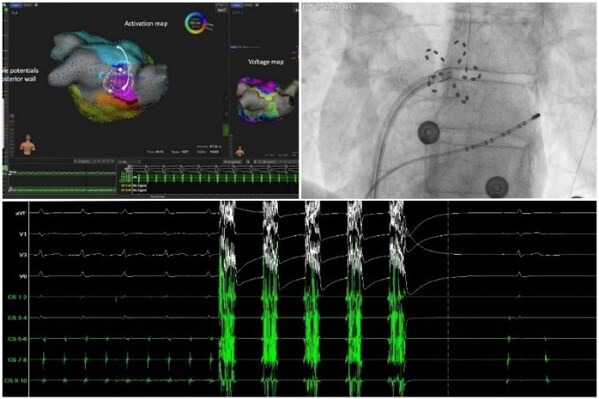

FARAPULSE脈沖電場(chǎng)消融新技術(shù)手術(shù)